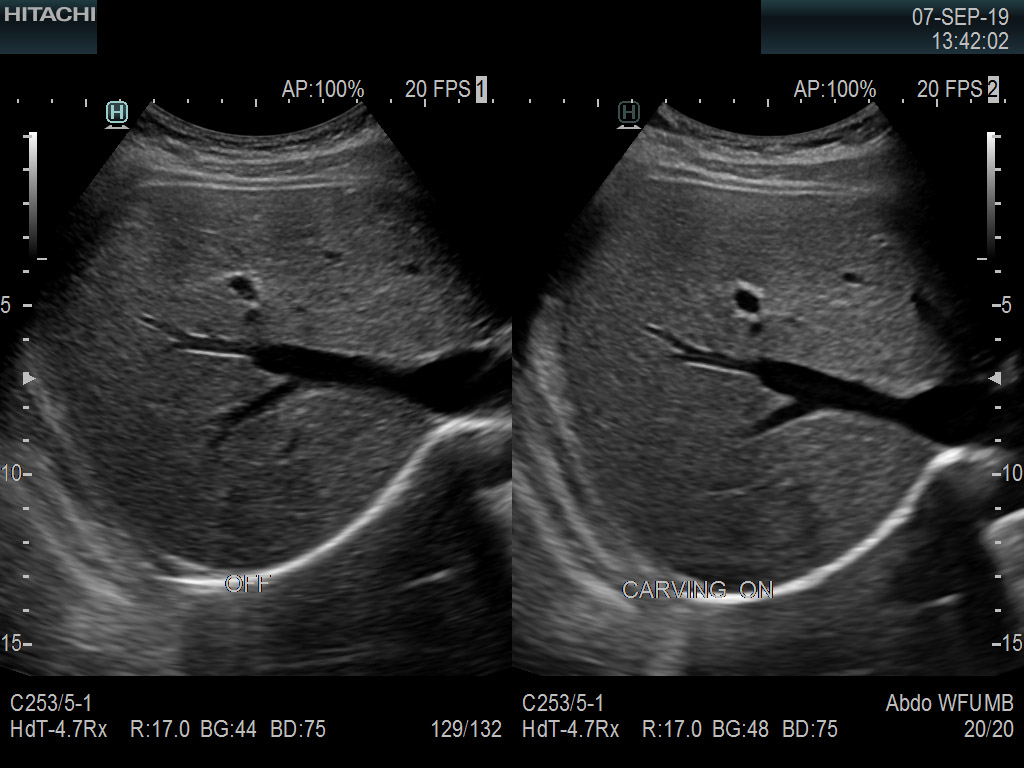

Recognized for our outstanding image quality, outstanding system reliability and intuitive use of cutting edge technology, Fujifilm Healthcare remains the standard in the field of Surgery.

Fujifilm Healthcare’s ARIETTA Precision features state-of-the-art digital architecture and advanced imaging technologies to redefine the capabilities of surgical ultrasound.

Imaging Clearly Defined

State-of-the-art digital architecture and advanced imaging features to redefine the capabilities of surgical ultrasound.